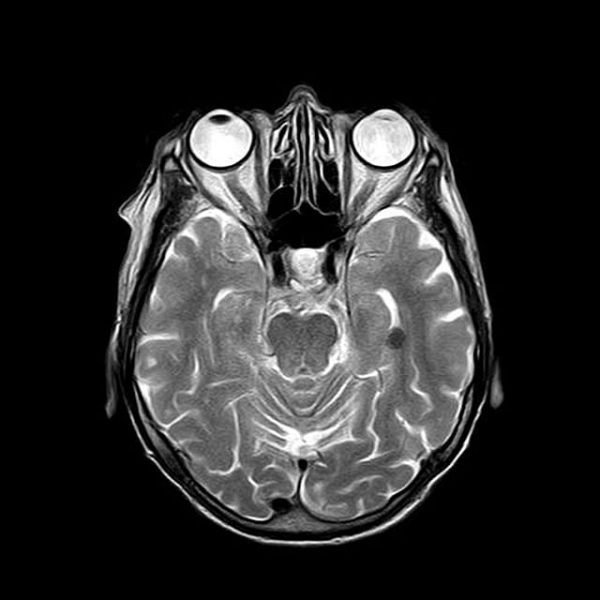

- Estudios con Imágenes Cerebrales: La resonancia magnética funcional (fMRI) y otras técnicas de imagen han mostrado cómo la práctica y el aprendizaje modifican la actividad y la conectividad cerebral. Por ejemplo, los músicos muestran cambios en las áreas del cerebro relacionadas con la coordinación y la audición.

- Terapias Basadas en Plasticidad: La comprensión de la plasticidad neuronal ha llevado al desarrollo de terapias para la rehabilitación de pacientes con lesiones cerebrales. La terapia de rehabilitación post-ictus, por ejemplo, utiliza ejercicios repetitivos para promover la reorganización cortical y la recuperación funcional.